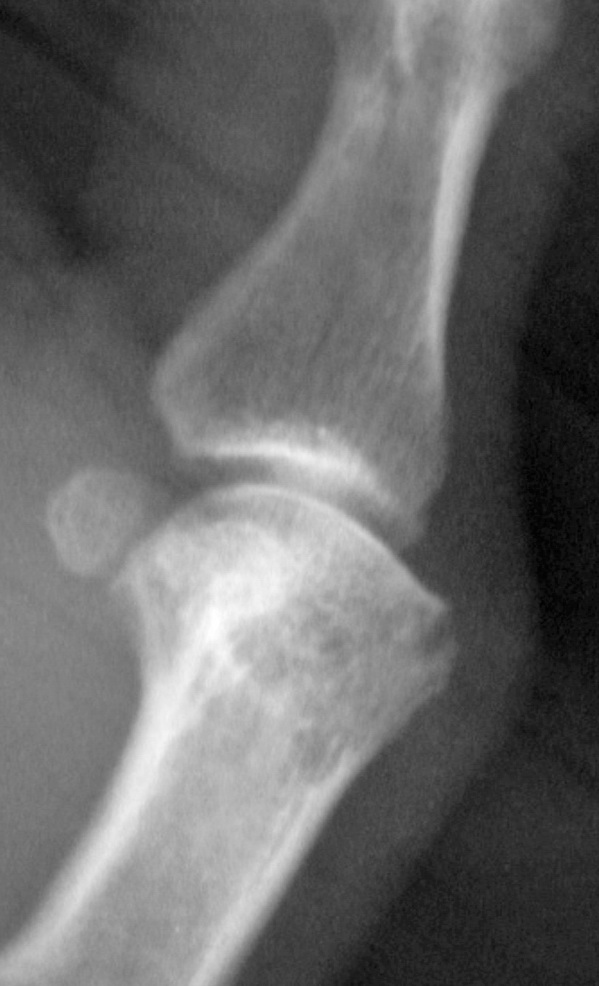

男,60,拇指掌指及指间关节疼痛15天。第一掌骨头低密度及箭头所指骨样突起正常吗

第一掌骨头局部低密度,考虑退变吧

手部经常可见囊状低密度区,可能为纤维性改变,无临床意义

箭头所指考虑纤维性骨皮质缺损。没有临床意义